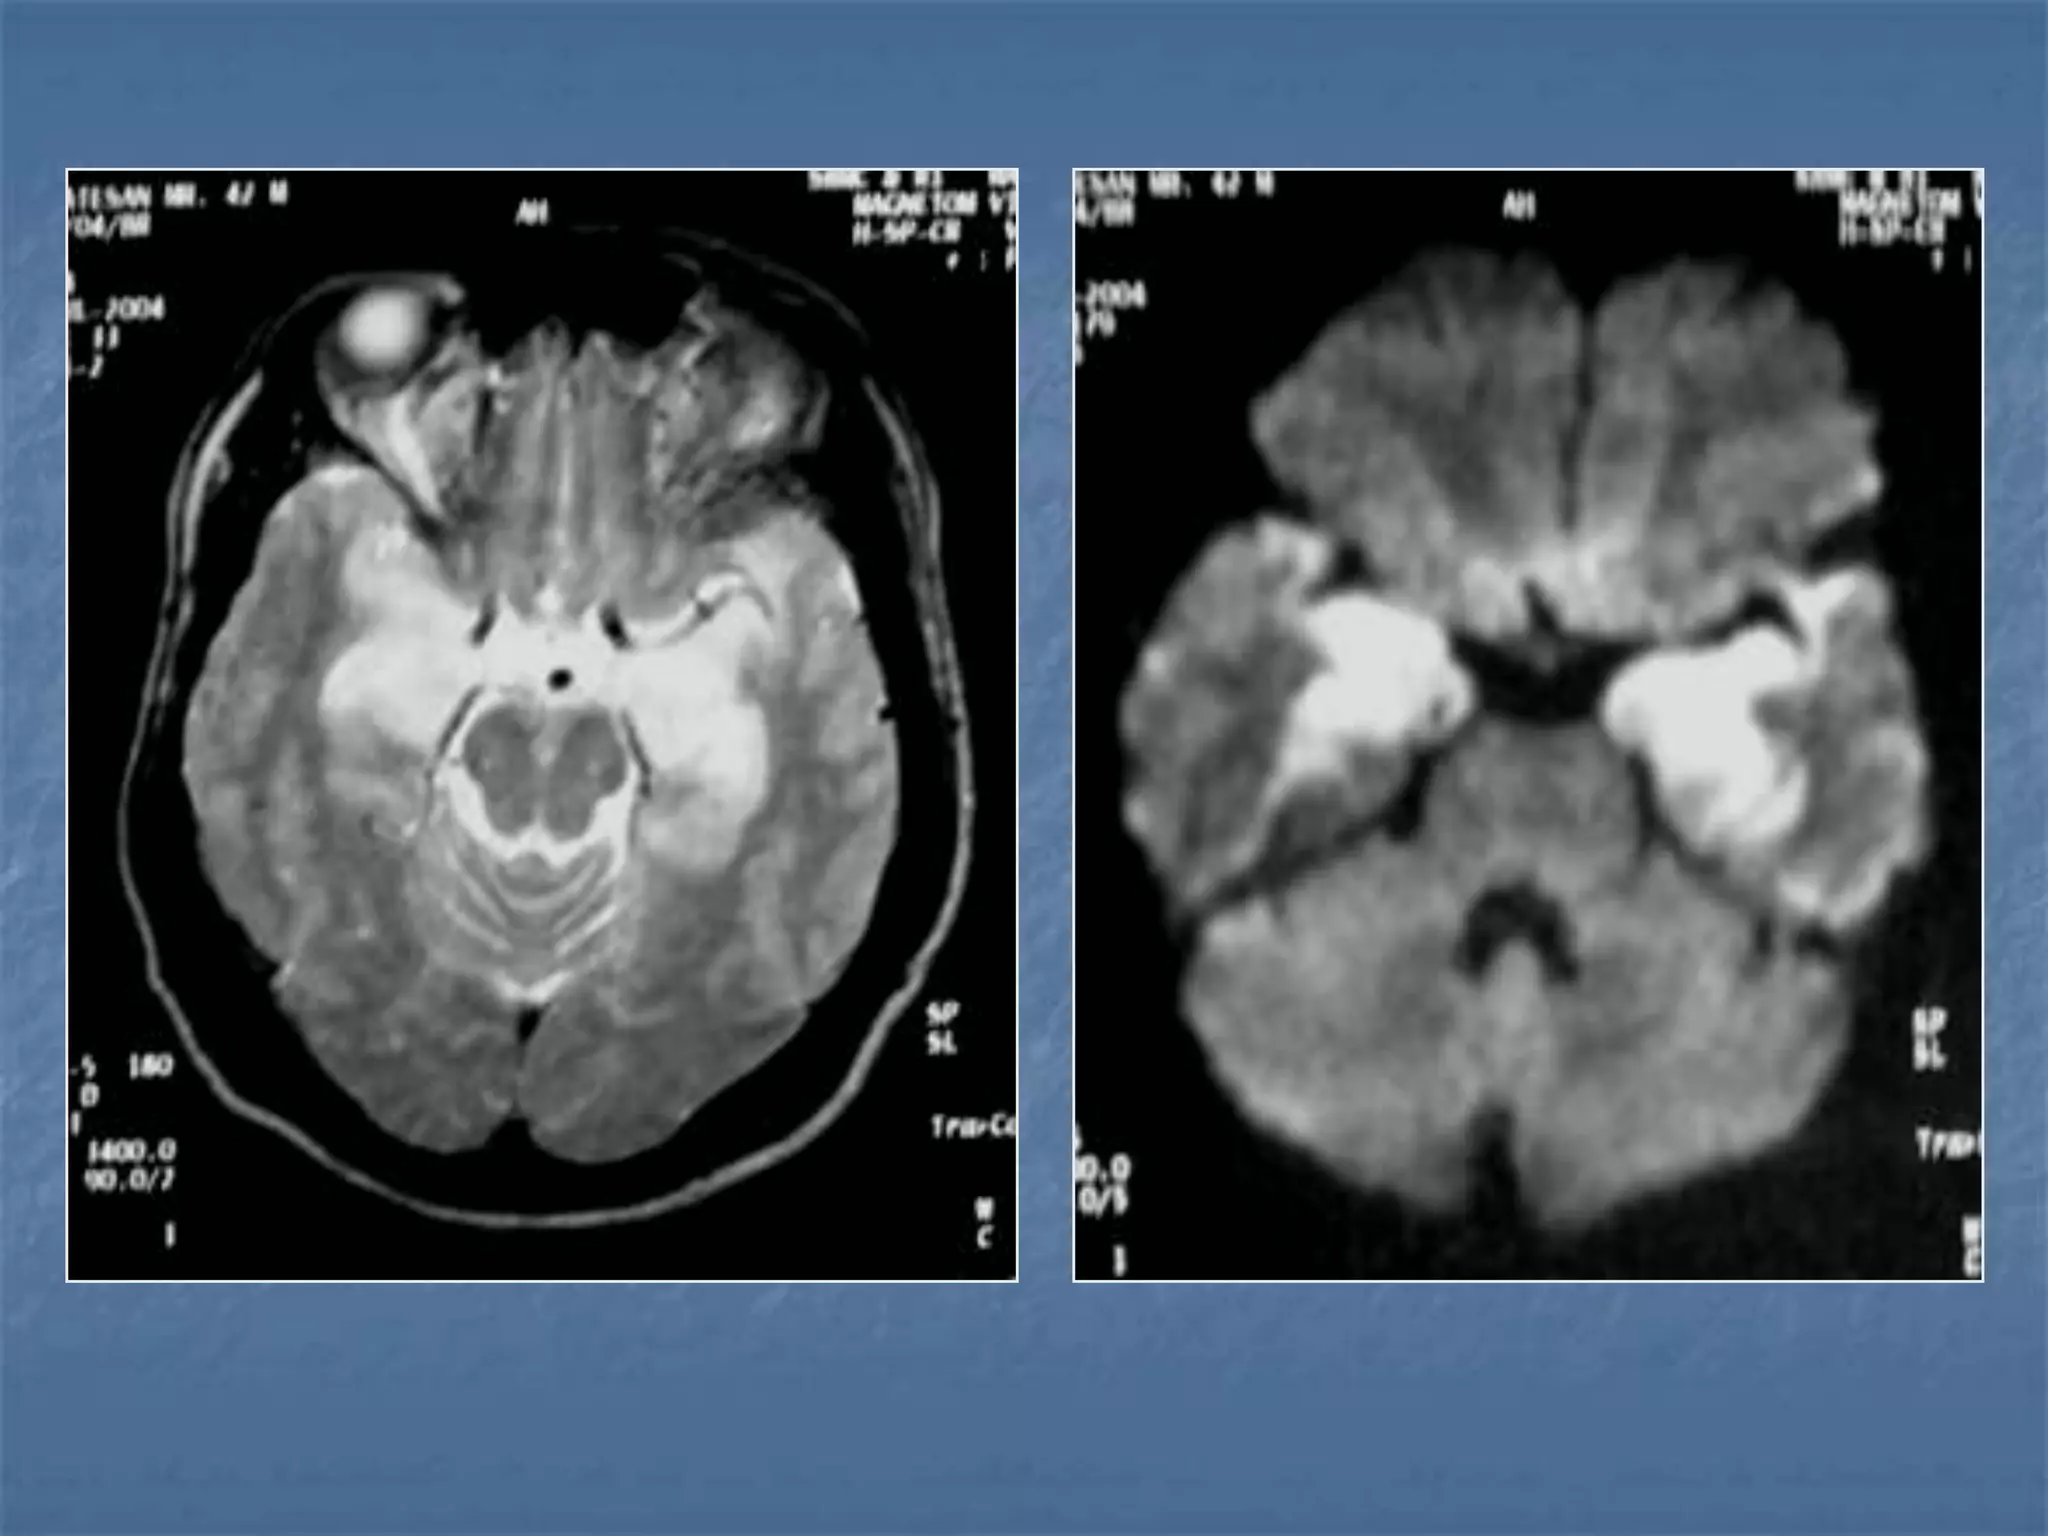

Diffusion Weighted Imaging

Radiology 2000;217:331-345

Detects Infarct As

Early As 15-30

minutes

AJNR 2003 ;24:878-885

• 46 patients with acute stroke

• CT and DWI within 6 hours

• Mean delay 24.5 min. (R 10–41 min.)

• EIC on CT - 33/46 (Sn 73%)

• DWI 42/45 - (Sn 93%)

CT vs DWI

 MRI has been increasingly utilized in

early stroke since it is more sensitive

than CT in the first twelve hours

 Bright on Diffusion weighted images

(detected as early as 15 to 30 min after

vessel occlusion).